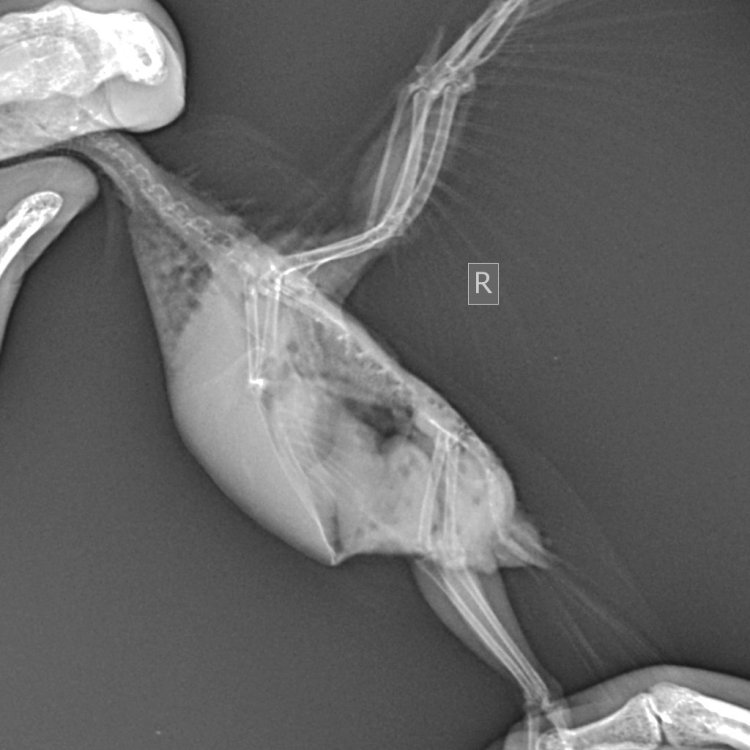

Здравствуйте. Помогите, пожалуйста, разобраться. Волнистый попугай, девочка, 3 года 5 месяцев. Лечили мегабактериоз, на вчерашней микроскопии ни одной мегабактерии, однако рвота и непереваренные зерна в помете остаются. Сделали рентген, орнитологи в замешательстве, у каждого свое отличное мнение по поводу преджелудка , печени и новообразовании в лёгких. В помете также нашли много пыльцы, однако возможно , что это глисты. Снова не понятно. Помогите , пожалуйста, разобраться с рентгеном и микроскопией. Фото прикладываю.